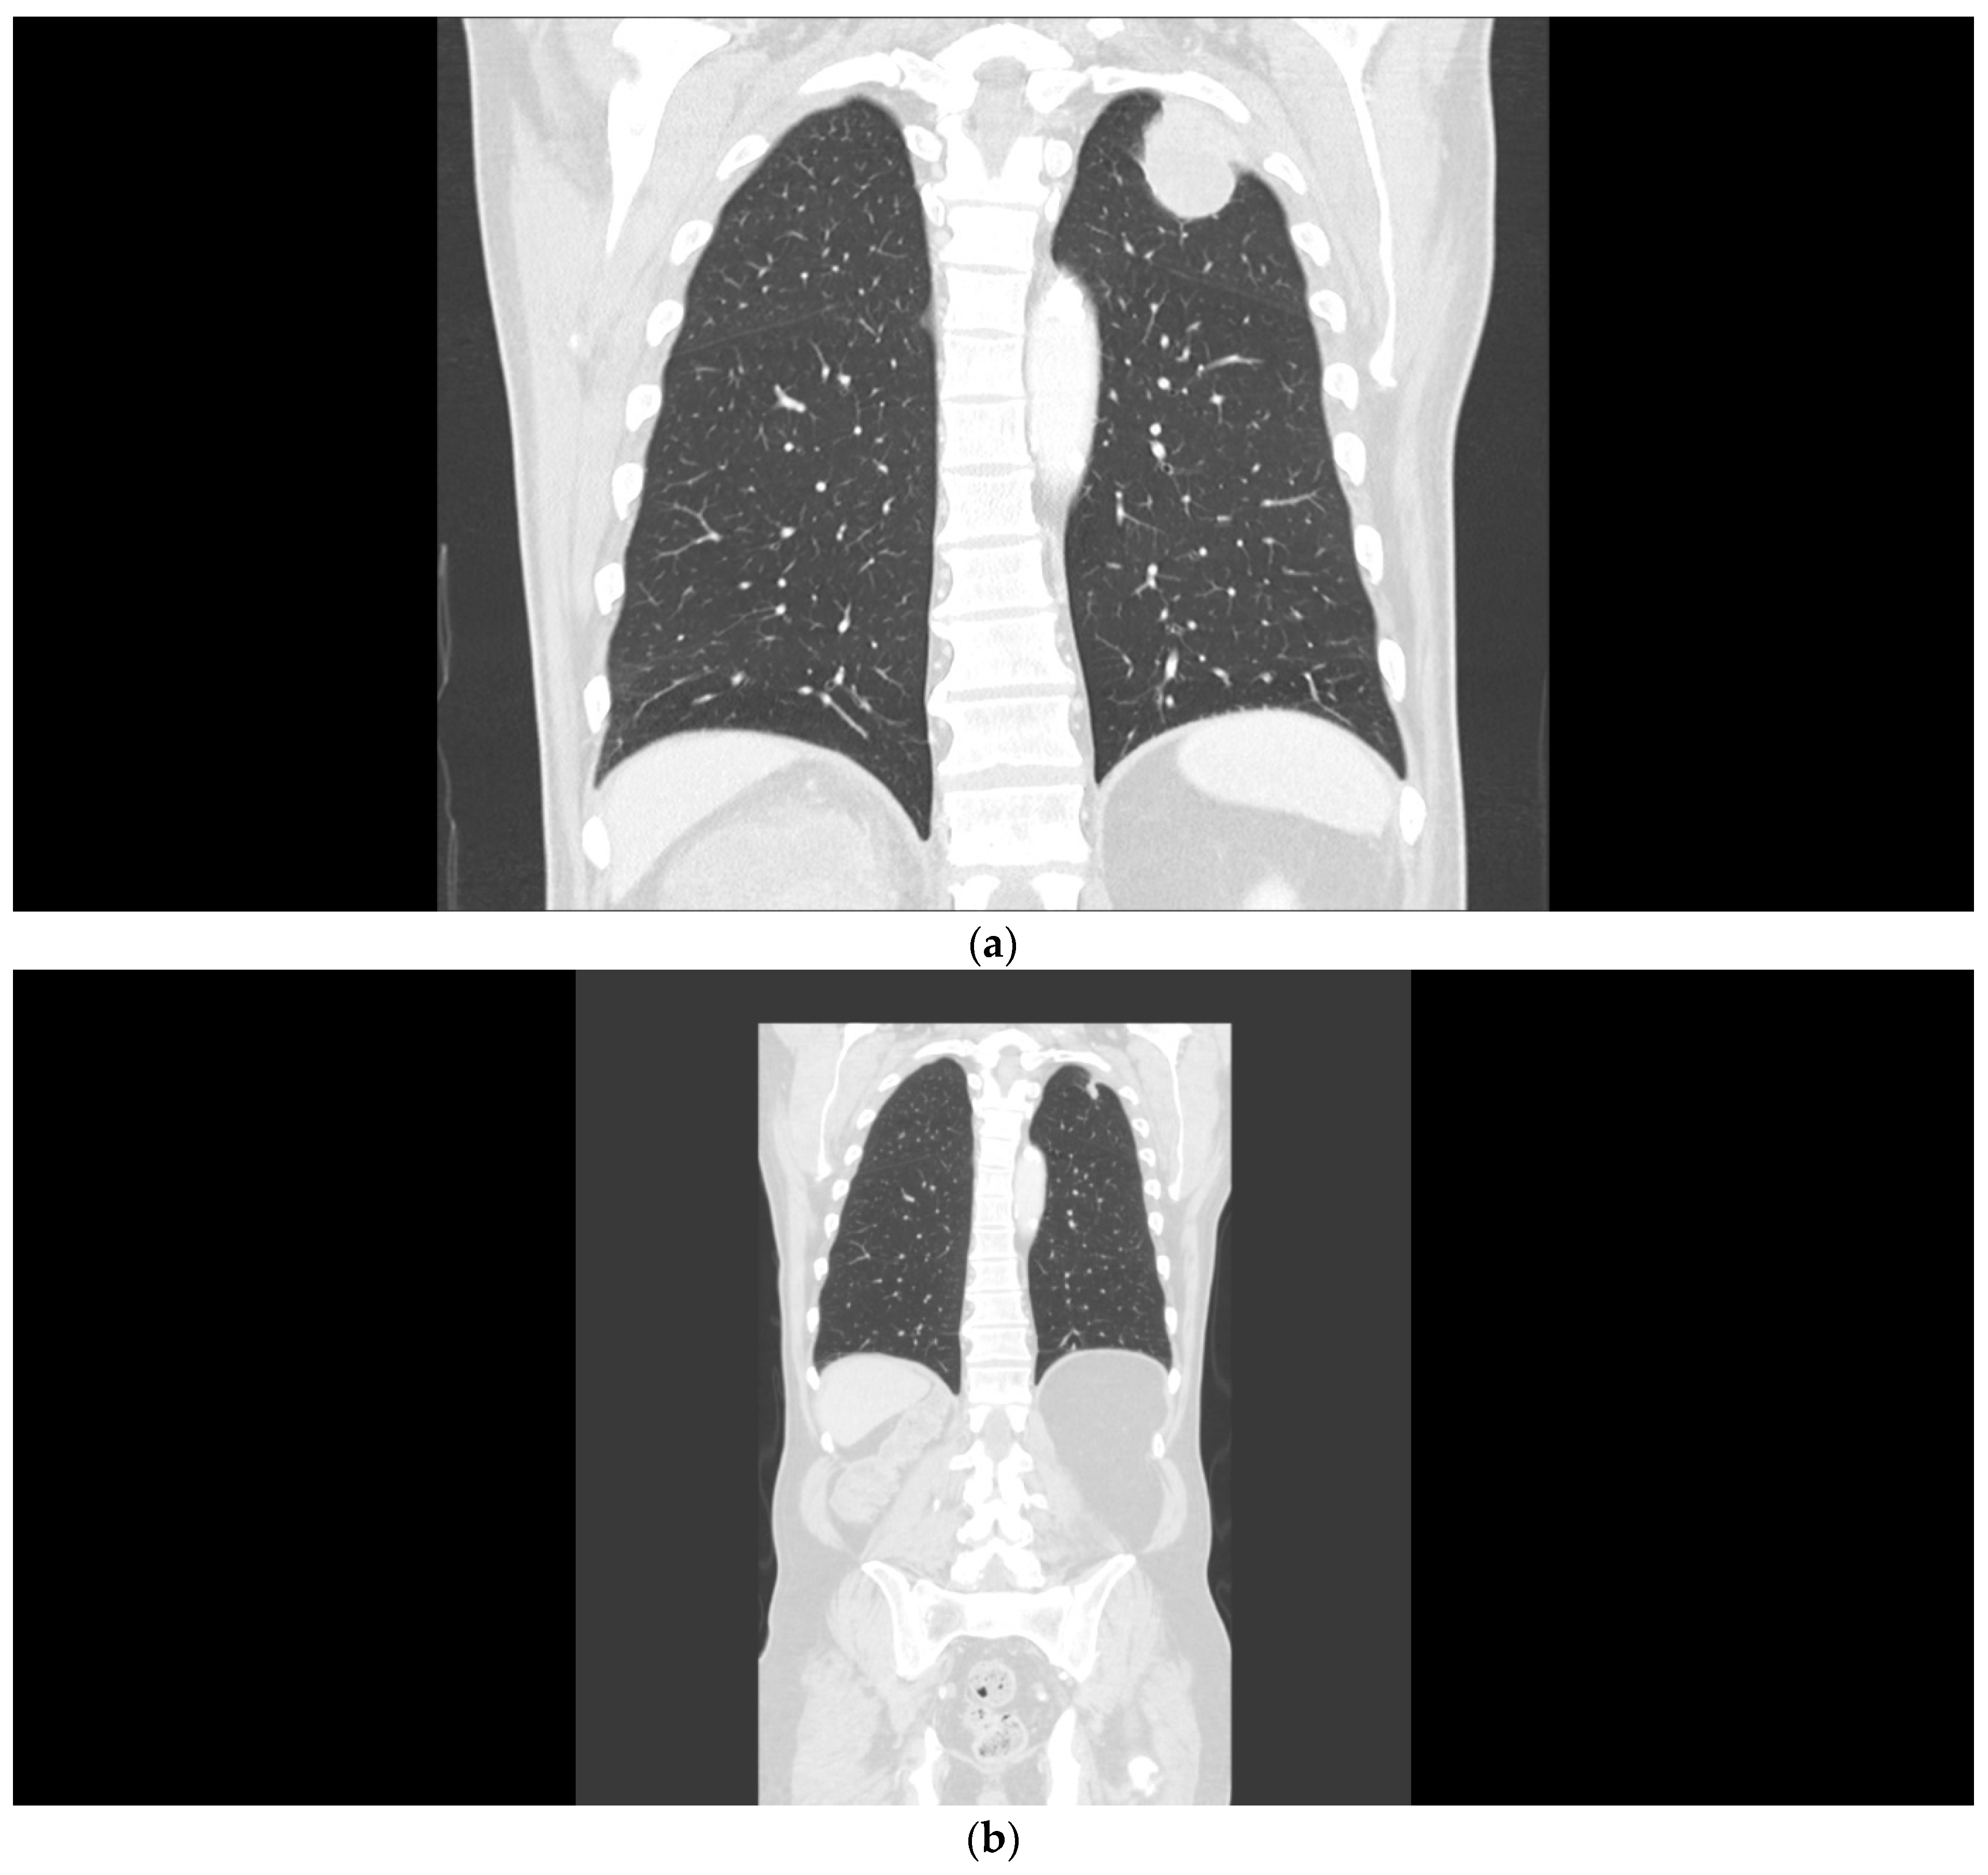

A 58-year-old male patient presented in November 2014 with a left renal mass and bulky retroperitoneal lymphadenopathy (Figure 2a). The patient had a short history of arterial hypertension and sinus tachycardia. Laboratory examinations at the time of diagnosis showed anemia, thrombocytosis, neutrophilia, and alanine aminotransferase (ALT) and aspartate aminotransferase (AST) CTCAE grade 1 elevation. The patient had the tumor removed in November 2014, but the surgery was only cytoreductive and not radical, leaving a left residual mass in the retroperitoneum. Histological examination revealed sRCC pT3pN1M0. A CT scan two months after surgery showed multiple lung metastases, 3 cm in size (Figure 2b), and a large mass in the retroperitoneum (Figure 2c). The patient had a poor prognosis score according to IMDC (anemia, neutrophilia, thrombocytosis, KPS, and interval to therapy initiation). The laboratory parameters of liver function improved after surgery and were within normal range. In March 2015, the patient was enrolled in the CheckMate 214 trial and received the combination therapy of nivolumab plus ipilimumab at a standard dose for four cycles, then continued with nivolumab monotherapy (3 mg/kg) every two weeks, achieving major partial response on CT examination within two months (Figure 2d). Soon after therapy initiation, the patient felt relieved, and his blood count was normalized. The patient continued with the therapy until October 2021, when the therapy was permanently stopped due to grade 3 ALT and AST elevation. Intravenous methylprednisone 1 mg/kg was immediately initiated. Liver tests gradually returned to normal, and all clinical symptoms accompanying the course of therapy that the patient did not consider, including grade 1 diarrhea, grade 2 insomnia, and grade 1 joint pain, disappeared. The patient continues to be followed. At the last visit in May 2022, he was without evidence of disease activity.

Figure 2.

(a) Patient 2, pretreatment CT of the renal tumor. (b) Patient 2, pretreatment CT of the chest demonstrating lung metastases. (c) Patient 2, a large mass in the retroperitoneum. (d) Patient 2, major partial response after the combination regimen of ipilimumab with nivolumab.